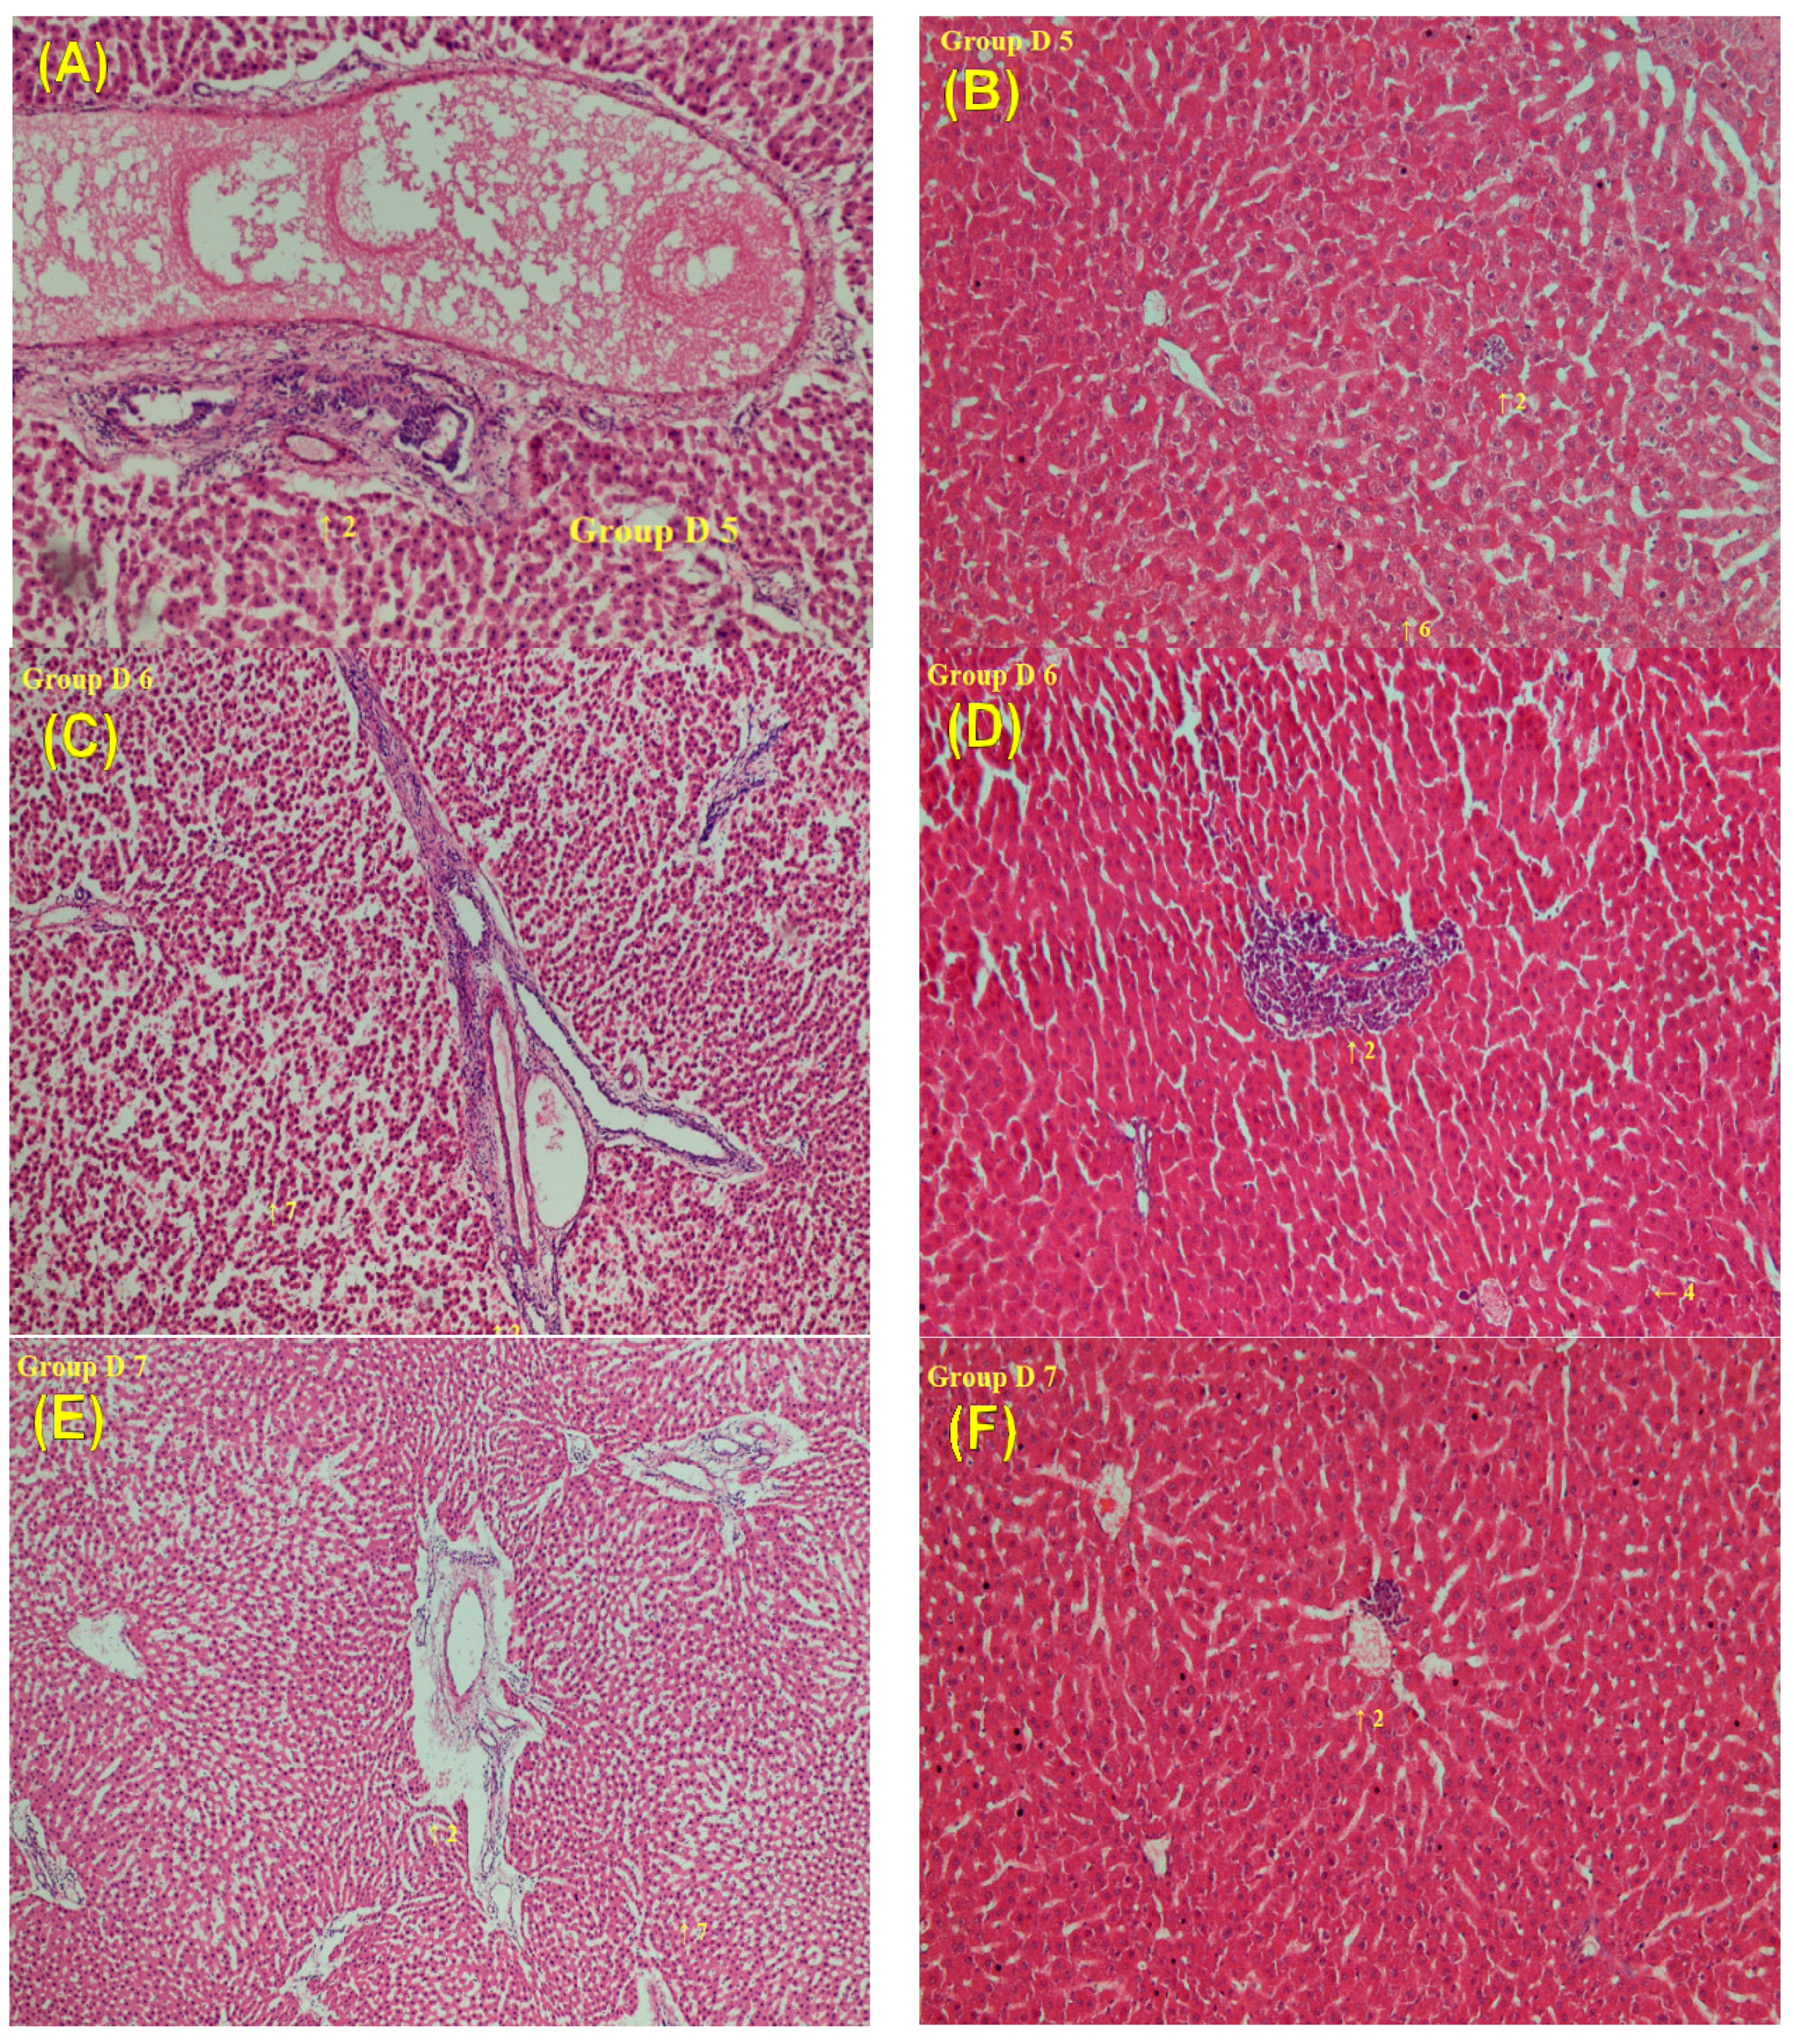

2.7. Histopathological Analyses after Treatment with Sorafenib and the LDXGT Formulation

- Group D5, repeated treatment with sorafenib (10 mg/kg) for 2 weeks.

- Group D6, repeated treatment with the combination of the LDXGT formulation (1 g/kg/day, p.o.) and sorafenib (10 mg/kg, p.o.) for 2 weeks.

- Group D7, repeated treatment with the combination of the LDXGT formulation (2 g/kg/day, p.o.) and sorafenib (10 mg/kg, p.o.) for 2 weeks.